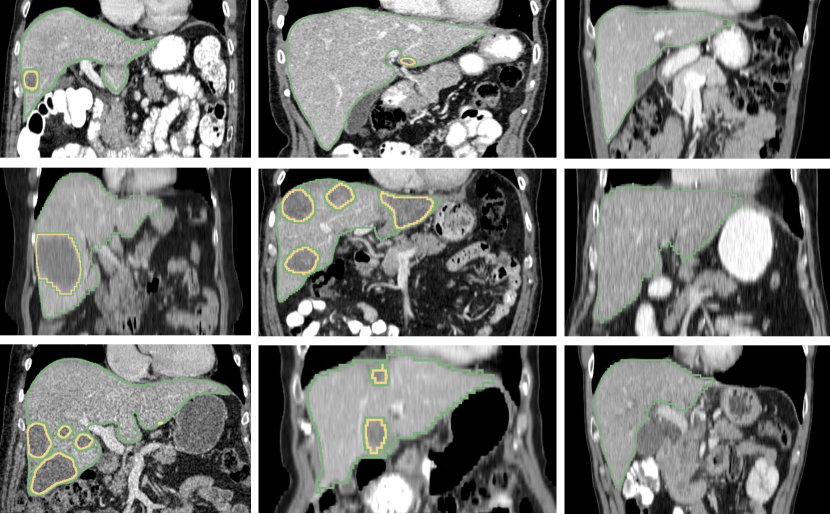

Appendix B Liver Tumor Segmentation Challenge

We show 9 example sagittal slices from the LITS challenge test set in Fig. 23 to demonstrate the variation of both livers and liver lesions. The images are cropped to the region with liver centered. The sizes and shapes of the livers vary a lot between individuals. The variation of liver lesion in sizes and intensities is even higher. The lesions are highly sparse in the abdominal CT images. Thus it is challenging for the networks to segment the lesions with small sizes. Please note that we do not have the ground truth of the test volumes.

Refer to caption

Figure 23: Example sagittal view slices from the LITS challenge test volumes overlaided with the segmentation boundaries obtained with 3D AH-Net. The livers and the lesions both vary in sizes, morphology and intensities.